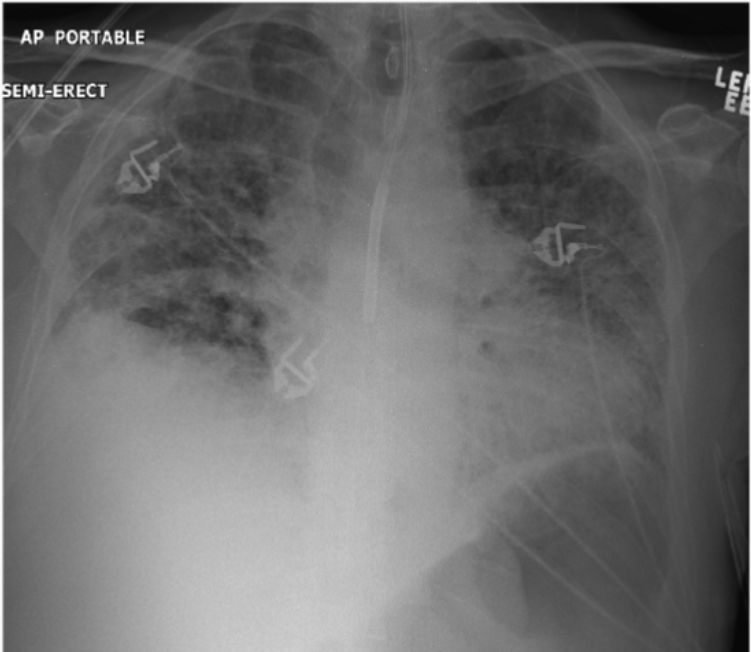

What was the patient’s original dx (left) and what caused improvement (right)?

Pulmonary edema- before (left) and after lasix aka “fluid pill” (right)